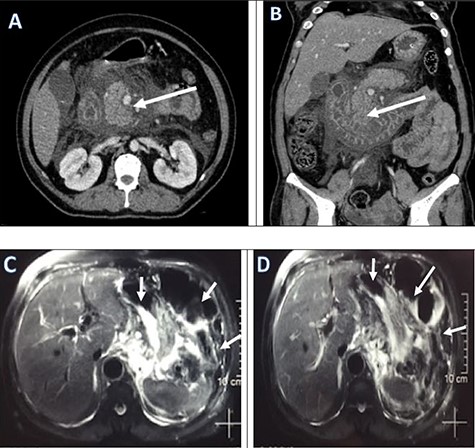

Regarding her management at emergency, an aggressive fluid resuscitation with compound sodium lactate 3 litres over half an hour was started. A foley’s catheterization followed by nasogastric tube (NGT) was inserted for gastric decompression. An immediate collection of 900 ml of non-bilious clear fluid was drained. The Rapid Diagnostic Test for COVID 19 infection was sent which showed positive. Then, she was transferred to the COVID-Intensive Care Unit (ICU) for ongoing fluid resuscitation and further management. The PCR test for COVID-19 was sent from ED which showed positive later that day. A broad-spectrum intravenous antibiotics, intravenous analgesics was started. A contrast-enhanced computed tomography (CECT) scan was performed to find out the pathology. Abdominal contrast-enhanced CT showed small indistinct area of hypo-density and hypo-enhancement in the uncinate process with extensive peri-pancreatic inflammation around the pancreas suggestive of acute necrotizing pancreatitis (ANP) (Fig. 1).

Pre-operative CECT abdomen pelvis (a, b) and MRCP (c, d) showing pancreatic necrosis and spread of inflammation around the pancreas as shown by red arrows.